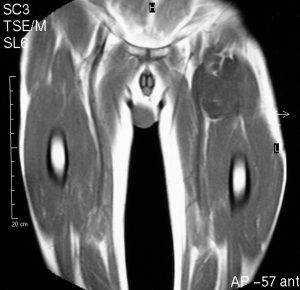

Сканирование КТ превосходит МРТ в детализации обследования поражений кортикальной кости и минерализации опухоли, в то время как МРТ является полезным источником информации для установления точной локализации опухоли на длинной оси конечности.

Большинство липосарком имеют четко определенные границы. Хорошо дифференцированные липосаркомы состоят в основном из жира с перегородками или узелками. Эти опухоли имеют гиперинтенсивное изображение, которое может повышаться от внутривенного введения контрастного вещества.

Миксоидные липосаркомы являются однородными или слабо неоднородными, может присутствовать псевдокапсула. Новообразования полиморфного типа имеют заметно неоднородную внутреннюю структуру. Гетерогенность опухолей и усиление контраста возрастает со степенью повышения их злокачественности.

67-летний мужчина с медленно растущей массой на левой ноге в области паха. Пациент некурящий и не диабетик. Низкий сигнал интенсивности.